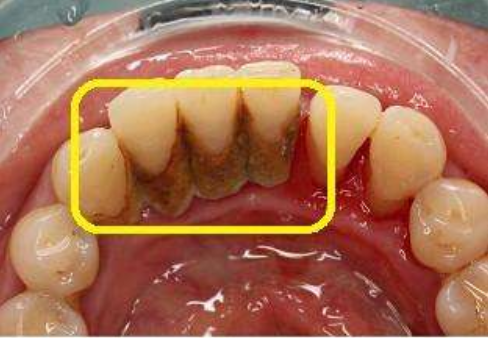

最容易堆积牙结石的地方在下中牙内侧,你如果从来没有洗过牙,现在只需要一面镜子就看到很多包围在牙齿表面的牙结石。

牙结石像一块烂泥渣,贴在齿龈交界处,并不断向下侵犯,牙龈出血就在这样的情况下发生的。

4、一个严重的问题:牙结石侵犯龈下

牙结石堆积在牙根上